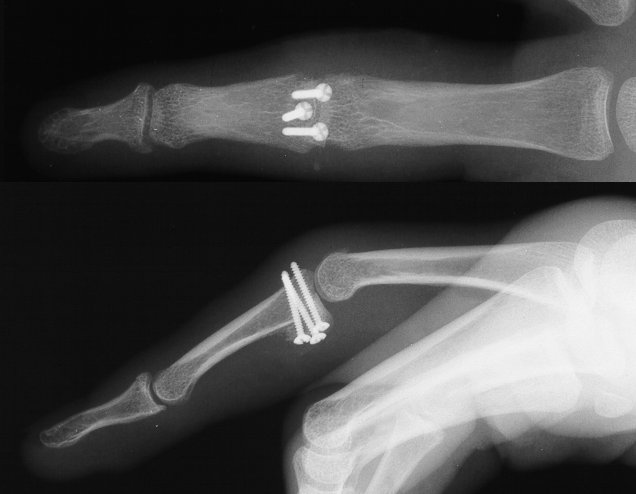

Xrays show a comminuted dorsal fracture dislocation of the proximal interphalangeal joint with dorsal subluxation.

These wires are then replace, one at a time with micro screws.

Click for larger image